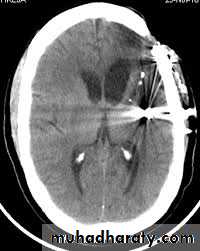

Imaging modalities used are as follows:1. Conventional radiography: it is a noninvasive, inexpensive modality;multiple views are needed (at least 2 views: anteroposterior andlateral).2. Computed tomographic (CT) scan: it has a very important role invisualizing and locating foreign bodies, even radiolucent ones; it alsoprovides information about local anatomy, tissue reaction, and abscess formation.

3. Fluoroscopy: C-arm imaging equipment allows for real timeradiographic visualization of the foreign body.4. Magnetic resonance imaging: it is used in nonmetallic foreign bodies; it provides detailed information regarding tissue reaction.5. Ultrasonography.

Management of retained needles requires locating the broken fragment through panoramic, computed tomographic (CT) scan or CBCT. The treatment options should be discussed with the patients. Retrieval usually is performed under general anesthesia. For broken needles embedded in the pterygo-mandibular space an intraoral approach through a vertical incision along the anterior border of the mandible,

extending inferiorly to the external oblique ridge, followed by sub-periosteal dissection along the medial aspect of the ramus of the mandible to identify bony landmarks (lingula), which can be used as

reference during exploration and also provides greater protection to the inferior alveolar and lingual nerves, supra-periosteal blunt dissection may be needed to identify the needle.